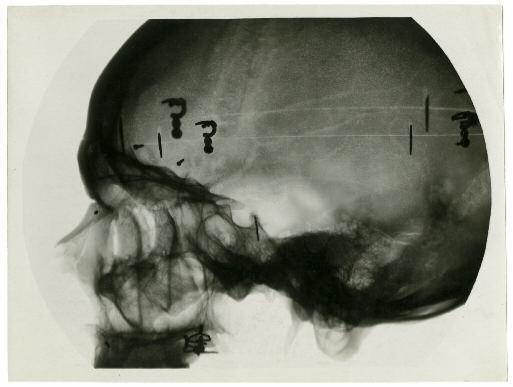

“Une nouvelle lumière crèe de nouvelles images”

: les rayons X de Röntgen permirent à des photographes comme Albert

Londe d’explorer les nouvelles possibilités dès les dernières années du XIXe siècle.

Un jeune étudiant francais en médecine, René Ledoux-Lebard, décide en

1906

de se consacrer à la généralisation

de la radiographie dans les hopitaux français. Pour convaincre les chirurgiens de la Salpétrière puis des autres

hopitaux de l’importance de lier Radiologie et photographie, il n’hésite pas à créer de grandes épreuves positives

qu’il expose lors de ses conférences.